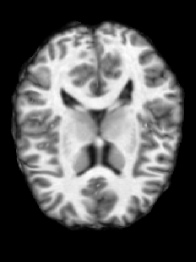

In a first step, we consider a pair of representative images of the OASIS-1 dataset. We show the registration results in Figure 3. We illustrate the computed spatial transformation in Figure 4. We report the DICE scores for the four ROIs in Table 1. We report additional performance measures in Table 2. We report measures for the difference of the composition of the forward map and its inverse from identity in Table 3.

Based on the results for registration accuracy reported in Table 1 and Table 2, we observe that all methods yield competitive results. This is qualitatively confirmed by the visualizations shown in Figure 3. Overall, VPreg yields a slightly better DICE score for the four anatomical regions considered in this study. Easyreg yields the best MSE-ratio and MI-incr. Overall, we conclude that our method is competitive in terms of registration accuracy for this exemplary pair of images.

If we turn to properties of the deformation map, we can observe that VPreg yields well-behaved maps. In particular, VPreg yields diffeomorphic transformations and at the same time provides an accurate approximation of their inverse. This can be seen qualitatively in Figure 4 and, more importantly, is quantified in Table 2 and Table 3. The maps generated by ANTs and Easyreg are not diffeomorphic as judged by the minimal value of the determinant of the Jacobian of the transformation in Table 2. Those generated by Fnirt are. We emphasize that the numerical guarantees on generating diffeomorphic maps VPreg provides do not negatively affect registration accuracy as confirmed by the DICE scores reported in Table 1. These observations are also confirmed by the visualizations shown in fig. 4.

Turning to the accuracy for computing the inverse map, we can observe that VPreg does yield inverses that are most consistent with the forward map. This is confirmed by the results reported in Table 3; the composition of the computed map and its inverse is much closer to for VPreg than for the other methods.